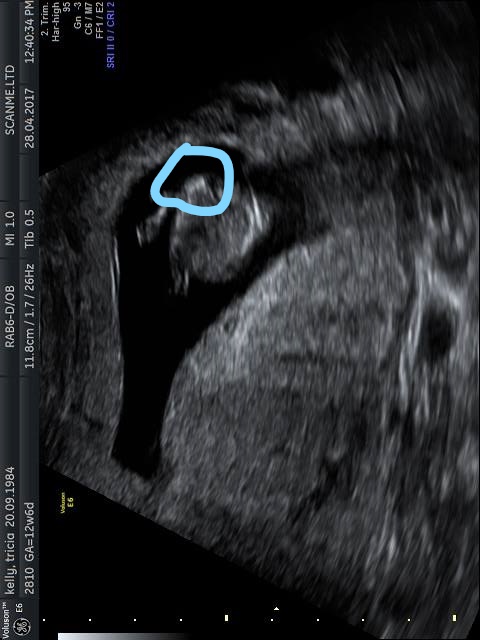

That looks girly to me, but not as great a shot as I like and also earlier gestation than I prefer to guess at. Good luck.

The nub view looks girly. Do you have more shots of it?

Did you hoped for a 7. Boy ;) i dont think your hope will come true ;) Looks very girly

Looks like a girl to me!